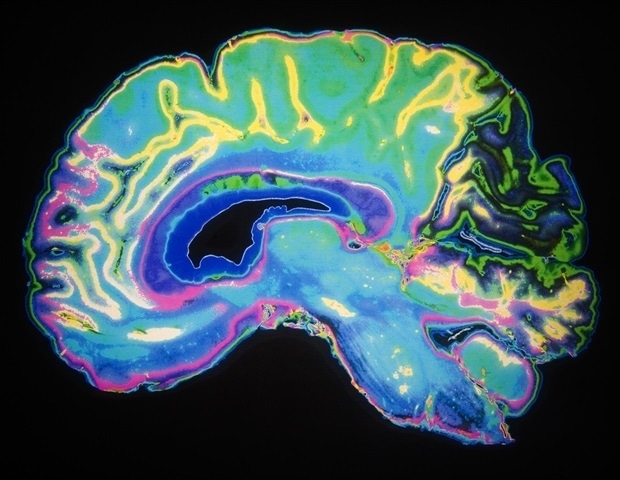

Паразит, который, возможно, уже живет в вашем мозгу, может заразить те самые иммунные клетки, которые пытаются его уничтожить, но новое исследование UVA Health показывает, как наш организм держит его под контролем.

Паразит, Toxoplasma gondii, потенциально смертелен. Он заражает теплокровных животных, но обычно передается людям через кошек или при употреблении зараженных продуктов или недоваренного мяса. Попав внутрь вас, паразит распространяется по всему телу и постоянно поселяется в мозгу. По оценкам, около трети всех людей во всем мире заражены этим паразитом, но, что удивительно, лишь немногие из них имеют симптомы. Заболевание, которое оно может вызвать, токсоплазмоз, в первую очередь представляет собой проблему для людей с ослабленным иммунитетом.